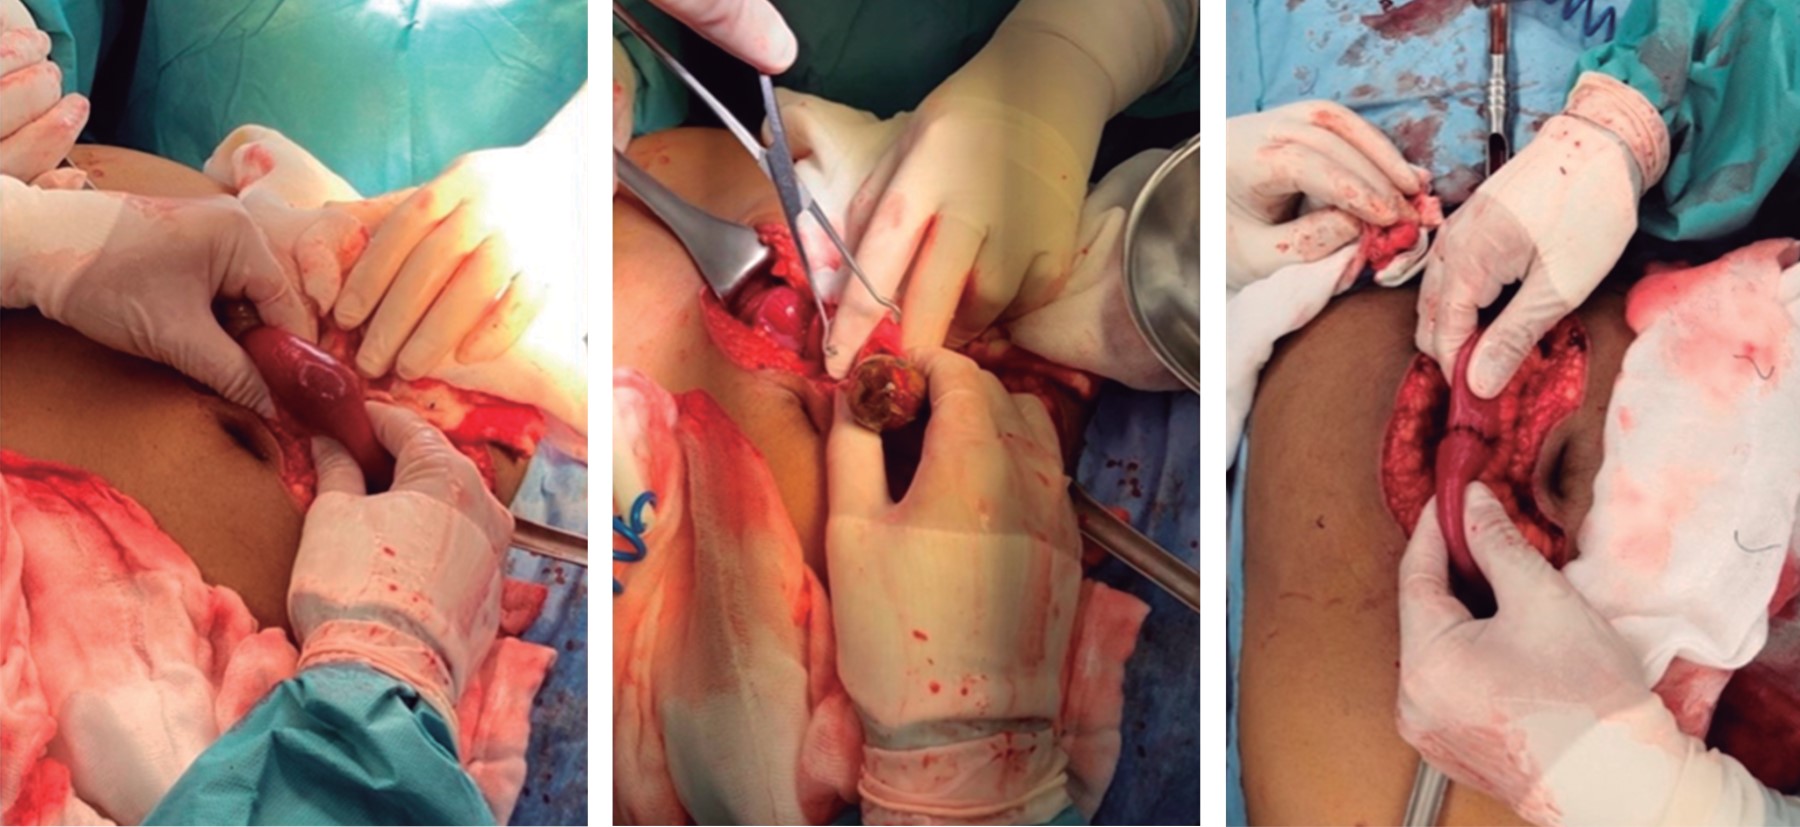

The transoperative findings were generalized distension of ileum and jejunum loops, and a 3 cm gallbladder litho impacted 90 cm from the ileocecal valve, which caused high intestinal occlusion. A healthy cecal appendix, a non-palpable gallbladder, and a scarce reaction fluid was found.

It was decided to perform enterolithotomy with the extraction of the litho and primary closure in two planes with the Connell-Mayo technique with polyglactin 910 3-0 atraumatic needle and an interrupted Lembert suture with silk and 3-0 atraumatic needle. The cholecystectomy as deferred (Figure 3). A half-inch Penrose-type drain was placed into the pelvic recess and closed in planes with a 0 polyglactin 910 sutures for the wall and skin closure by simple stitches with Nylon Preto 3-0 monofilament.

The treatment of this pathology is surgical; however, it starts with rehydration measures and correction of acid-base and electrolyte imbalances. There are two therapeutic options: on the one hand, enterolithotomy with stone extraction and deferred cholecystectomy, and on the other hand, enterolithotomy with cholecystectomy and fistula closure in a single surgical procedure.2,3,8 The first option represents less surgical risk and is often preferred since they are elderly patients with multiple comorbidities, and it is performed more frequently.1,3 Despite not being a patient with comorbidities and being stable at the time of the surgical event, we decided to perform a longitudinal enterolithotomy in the antimesenteric border of the ileum with transverse enterorrhaphy in two planes and cholecystectomy in a second surgical time, since we consider that this one has better results based on what has been reported in the literature.

Figure 3